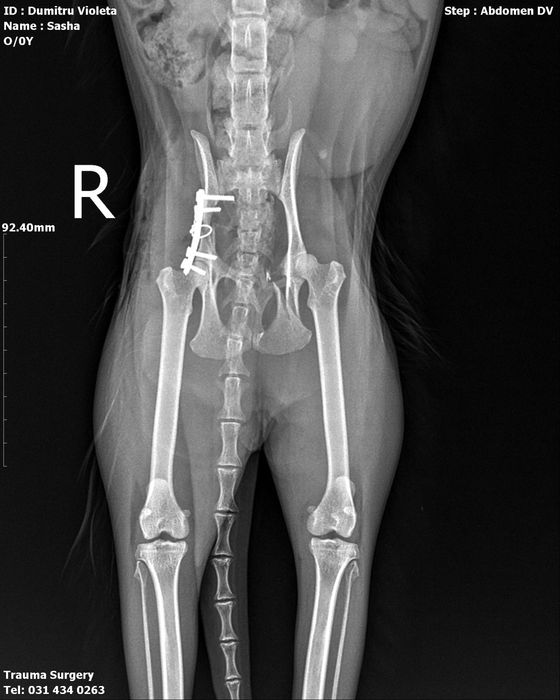

Sasha este o pisică de 6 ani, extrem de iubitoare, care a supraviețuit unui accident grav. A avut bazinul rupt, dar datorită unor oameni inimoși a fost operată, iar acum se recuperează frumos și începe să se miște din nou.